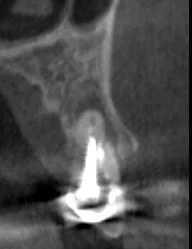

Давайте сравним снимки зубов, сделанные при помощи визиографа (слева), и при помощи компьютерной томографии (справа).

Как говорится, ощутите разницу. КТ - гораздо более точная и своевременная диагностика.

Воссоздавая орган (зуб) или даже совокупность органов, необходимо предельно точно знать исходную ситуацию. Корни зубов, каналы зубов, крупные сосудисто-нервные пучки, идущие внутри костной ткани, верхнечелюстная пазуха во всех подробностях и т.д. - в неискаженном виде все это можно увидеть только на компьютерной томограмме. Стоит ли говорить, что все эти структуры важны для имплантации, так как могут быть легко поврежденфы в ходе операции.